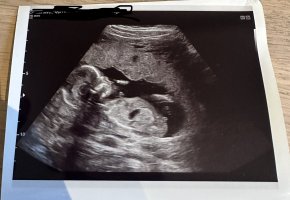

Ser ut som jente ut i fra nub på første bildet (jeg er ikke ekspert)![]()

Det viste seg for å være en gutt her!Ser ut som jente